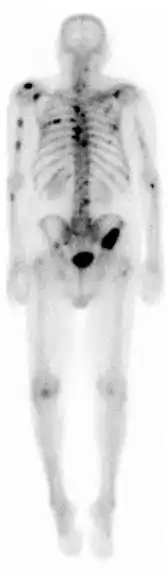

A nuclear medicine whole-body bone scan. The nuclear medicine whole-body bone scan is generally used in evaluations of various bone-related pathology, such as for bone pain, stress fracture, nonmalignant bone lesions, bone infections, or the spread of cancer to the bone.